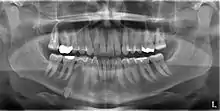

Mandibular canine impacted in the chin